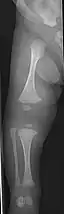

Right femur

Four X-rays of a 24-year-old American man, who had had more than one hundred bone fractures in his lifetime, and received a childhood clinical diagnosis of type IV–B OI. Genetic diagnosis in 2018 identified a previously uncatalogued pathogenic variant in the gene which encodes proα2(I) chains of type I procollagen, COL1A2, at exon 19, substitution c.974G>A. Due to childhood neglect and poverty, subject never received surgery to implant intramedullary rods. Malunions are evident as the humerus and femur were broken in adolescence but orthopedic care did not follow. Severe scoliosis, as well as kyphosis, are also evident. The unavoidably low contrast in the film is due to a combination of subject's obesity and low bone mineral density (BMD). Subject's BMD Z-score was -4.1 according to results of a dual-energy X-ray absorptiometry (DXA) scan also done in 2018.